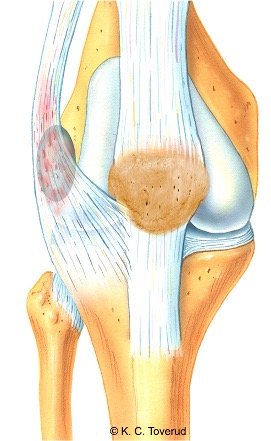

Kne, recessus suprapatellaris

Mange tilstander i kneleddet er utløst av traume. Det er derfor veldig viktig at man i anamnesen tar hensyn til gamle eventuelt nylig oppståtte traumer. I den eldre befolkningen er kneleddsartrose den vanligste tilstanden. Klinikken er sammensatt av smerter ved aktivitet og ofte leddhevelse. Ved klinisk undersøkelse foreligger det ofte et kapsulært bevegelsesmønster ved passive tester (mer redusert fleksjon enn ekstensjon). Hydrops testes med patella dip test.